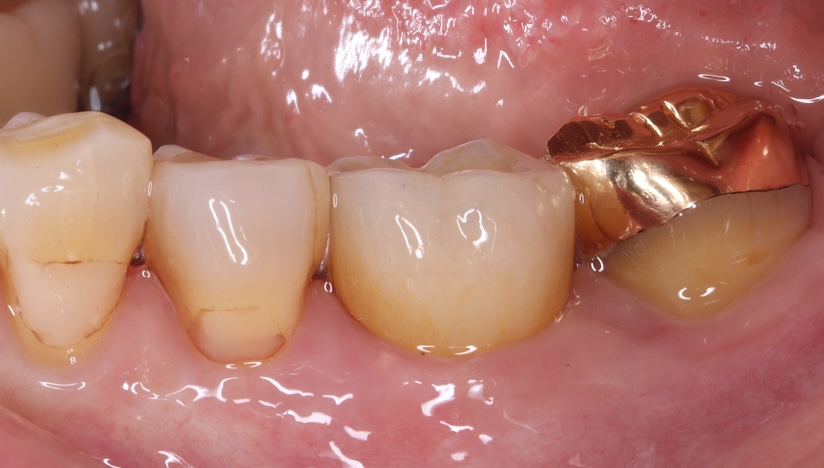

臼歯部(奥歯)単独インプラントで

他の天然歯を守った症例

タップで写真の拡大ができます。

主訴

噛むと痛い、歯茎が腫れてきた

治療内容

抜歯即時インプラント埋入、リッジプリザベーション(顎堤温存術)

治療期間

6〜8ヶ月

治療費用

649,000

治療の

リスク

オッセオインテグレーションが得られなかった場合、撤去、再度埋入の可能性